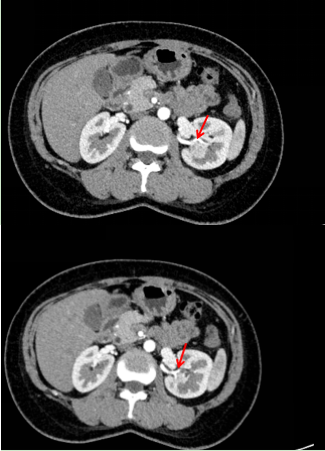

李女士入院以后,医生详细了解了她的病史。检查显示李女士的双侧肾脏功能良好,如果保肾手术成功,患者的获益很大。然而李女士体内肾肿瘤的RENAL评分为9分,RENAL评分越低则保肾的可能性越高,国际上认为RENAL评分>7分的患者更倾向于行根治性肾全切术。因此,浦金贤主任组织了科室内会诊,与多位主任一起对手术方案和步骤反复论证,充分预估手术过程中可能发生的意外情况,积极完善术前准备,也和患者及其家属进行了有效的沟通。

左肾肿瘤的冠状位、横断位、矢状位增强CT图像

肿瘤上极毗邻肾动脉的两个分支